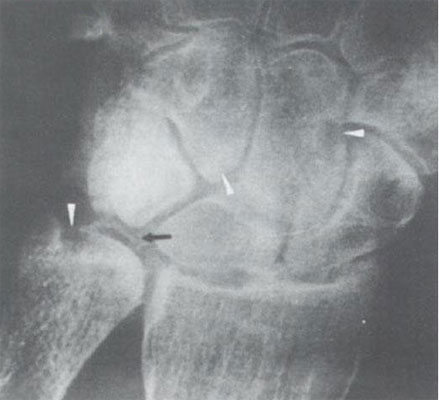

照片名称:肾性骨营养不良,cppd